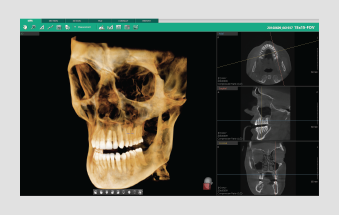

• 3D panorama

• Teeth mode

• Bone mode

• MIP mode

Quickly and easily switch between multiple VR views